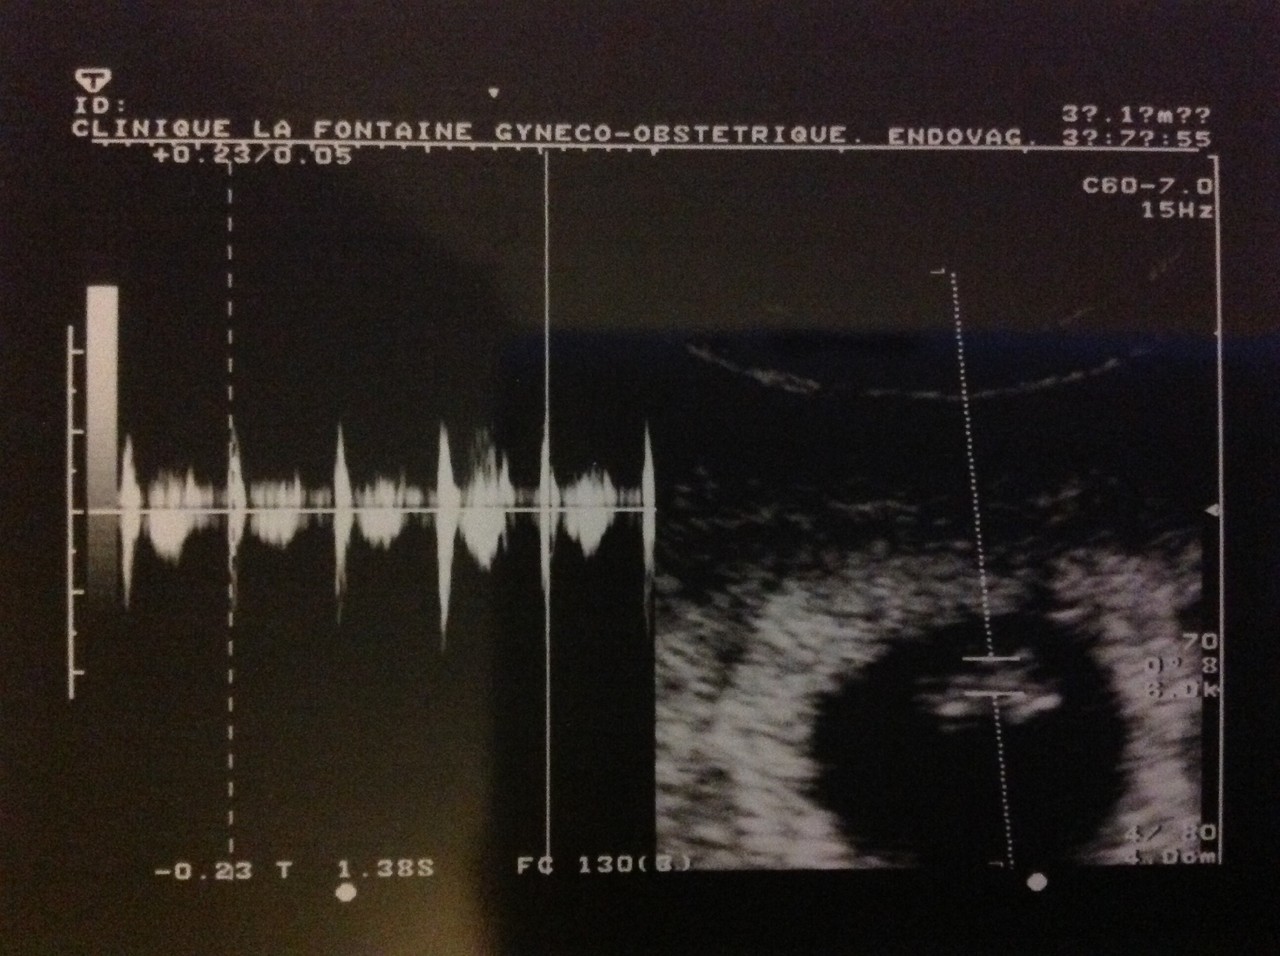

O PRIMEIRO RETRATO

Hoje faz exactamente um ano que o Gui tirou o seu primeiro "retrato"...

A primeira vez que o vimos...

A primeira vez que ouvimos o seu coraçãozinho bater...

Um momento único que ficará guardado para sempre!